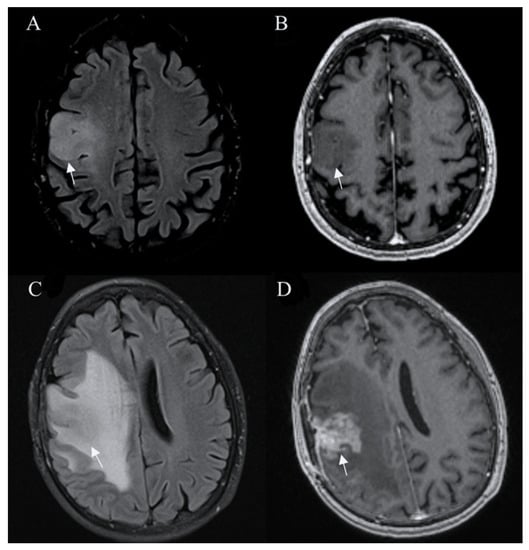

Standard Imaging Sequences